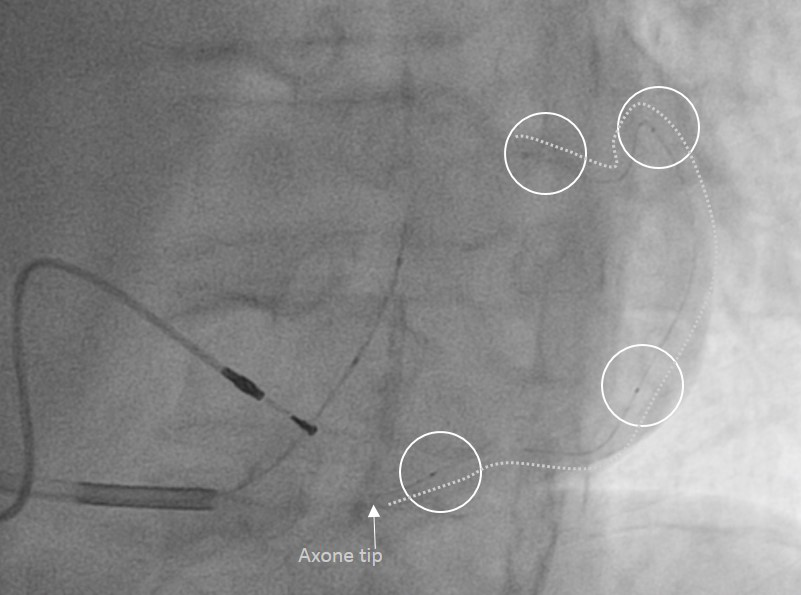

Axone ™起搏电极导线植入示意图

Axone ™起搏电极导线在人体内急性期性能的临床研究手术中穿过冠状静脉系统

目前,微创®心律管理正在进行Axone™起搏电极导线在人体内急性期性能的临床研究,并计划在今年底之前启动其长期性能的临床研究。Axone™起搏电极导线一旦成功应用于临床,将有望为心力衰竭患者提供更优化的心脏再同步化治疗解决方案。